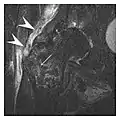

Figure 7: Fatigue fracture of the talus in a 25-year-old male basketball player with right hind foot and ankle pain, without history of trauma, and a normal initial radiograph (not shown). (a) One-month followup lateral radiograph shows normal appearance. (b) Sagittal T1-weighted MRI shows an irregular fracture line (arrow) within an ill-defined area of hypointensity corresponding to bone marrow edema.[1]